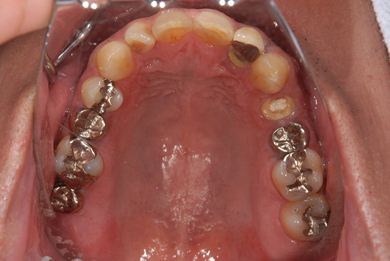

インプラントの症例写真 IMPLANT

抜歯即日スピードインプラント治療

| 性別/年齢 | 男性 / 36歳 | ||||||||||||||||||||||||||||||||

| 主訴 | 前歯が折れていてないので、インプラント治療を希望。 | ||||||||||||||||||||||||||||||||

| 治療内容 | インプラント1本(抜歯即日スピードインプラント)、ハイブリッドセラミッククラウン1本 | ||||||||||||||||||||||||||||||||

| 総治療費 | 257,250円 | ||||||||||||||||||||||||||||||||

| 治療期間 | 7ヶ月 |